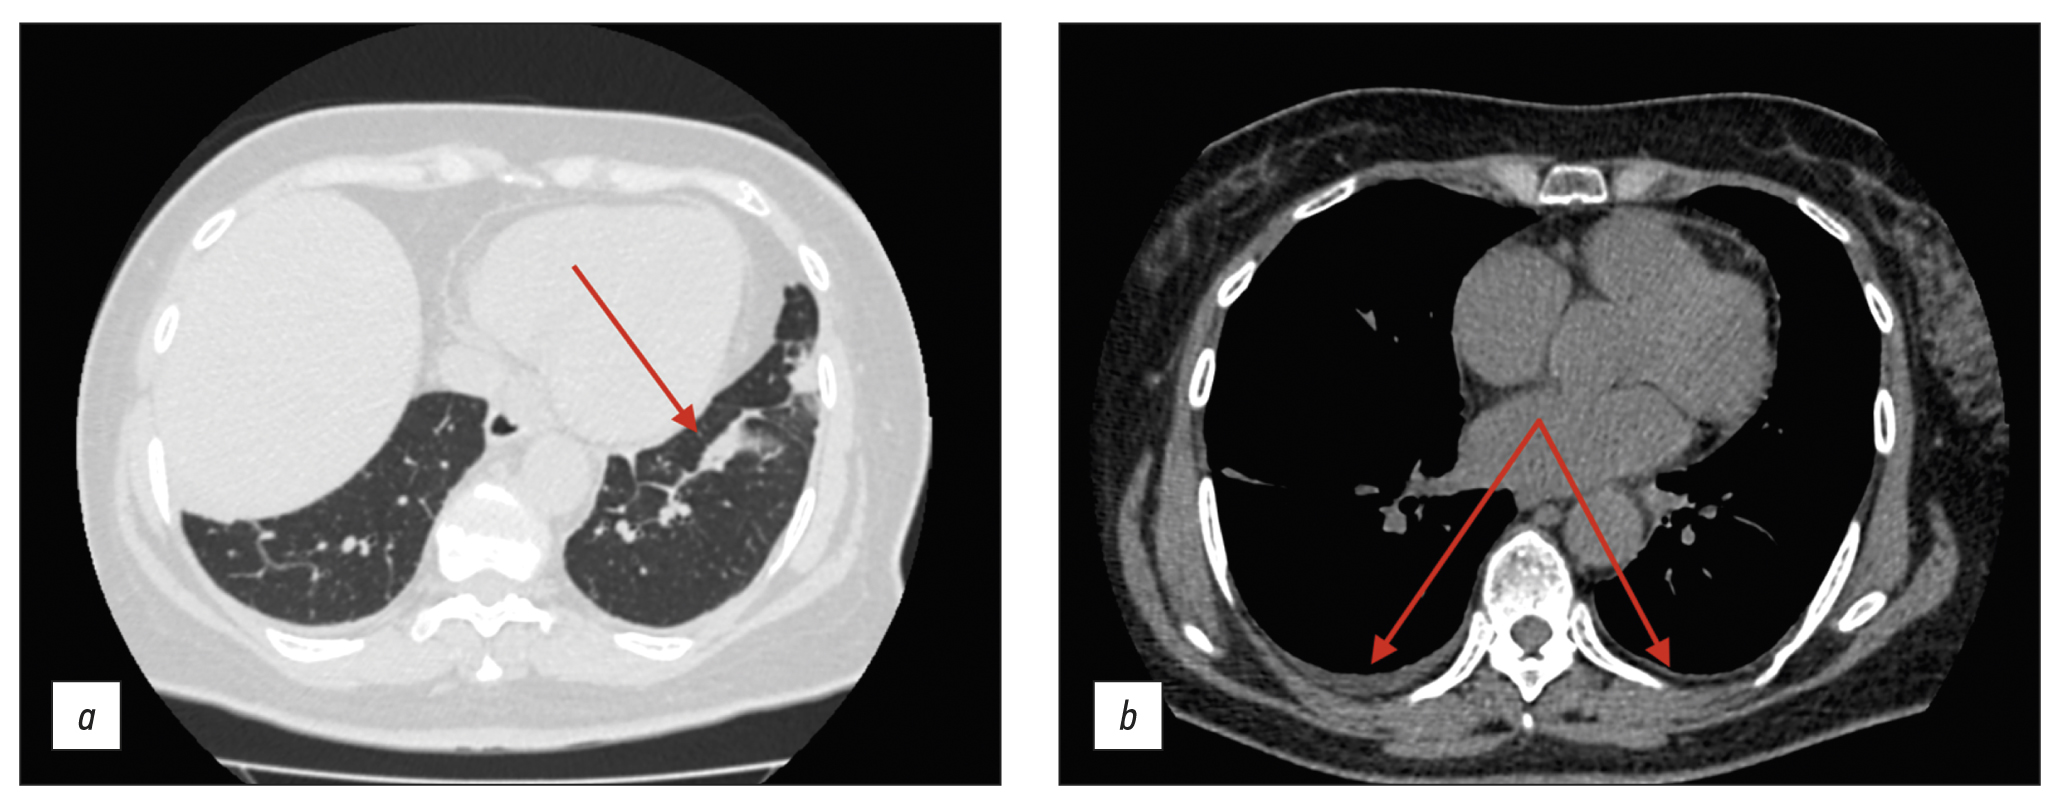

A 61-year-old woman presented to the hospital with a nocturnal fever up to 39.5°С, accompanied by chest and scapular pain, and substantial weight loss (10 kg over 3 months). Lymphoproliferative and infectious diseases were excluded. Baseline colonoscopy had revealed erosions in the colonic mucosa, leading to a preliminary diagnosis of ulcerative colitis, and subsequently, the patient was admitted to the gastroenterology department. Follow-up colonoscopy had excluded this diagnosis. Additional imaging via chest and abdominal computed tomography scan revealed wall thickening of aorta and its branches with subtle contrast enhancement.

Conditions, such as tuberculous aortoarteritis and syphilitic aortitis, were excluded. The patient was diagnosed with giant cell arteritis involving brachiocephalic trunk, subclavian arteries, and celiac trunk. Prednisolone was administered with subsequent reduction in symptoms.